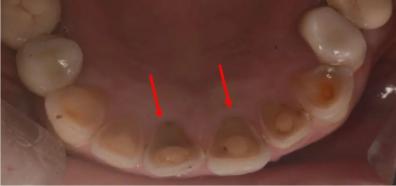

嘔吐過程中,伴隨食物的,還有高酸性的胃液從口腔中噴涌而出。胃液的酸度越高,對(duì)牙齒的腐蝕性越強(qiáng)。

最輕度的影響,是牙齒的敏感。這是由于牙齒最表層的牙釉質(zhì),受酸腐蝕,發(fā)生破壞。

隨著酸蝕進(jìn)一步加重,門牙從切緣(也就是咬切食物的這一條邊)開始缺損。這是由于門牙與胃液接觸最多。

再加重的話,上排的前牙,正反面都變薄變短。